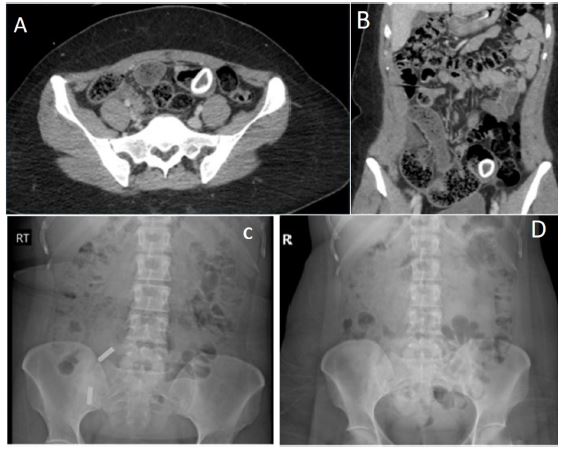

Figure 1: (A) Axial view of the CT Abdomen/Pelvis with IV contrast done the day of admission showing dilated distal small bowel loops and a ring-shaped high density in the mid to distal small bowel. No clear transition point is seen. (B) Coronal view of the CT Abdomen Pelvis with IV contrast done the day of admission showing dilated distal small bowel loops and a ring-shaped high density in the mid to distal small bowel. No clear transition point is seen. (C) Abdominal X-ray from the day of presentation showing nonspecific bowel gas patter and moderate diffuse constipation. Two radiopaque foreign bodies in RLQ were seen which were artifacts caused by objects from the outside. (D) Repeat abdominal X-ray one day after presentation showing unchanged bowel gas pattern and mild stool burden. Foreign body seen on CT scan is not visible on the X-ray.

After one day, the patient’s condition had not improved, and she had not had a bowel movement. To assess the status of the foreign body and determine if it was visible and in transit compared to the previous CT scan, an abdominal X-ray was obtained. An X-ray performed the previous evening did not reveal any foreign body (Figure 1).

The patient continued with an inability to tolerate the diet, prompting a decision to proceed with diagnostic laparoscopy, which revealed a Meckel’s diverticulum containing a large fecalith, necessitating conversion to open surgery with a supraumbilical mini laparotomy. Now extracorporeally, the diverticulum was mobilized, and the small bowel was transected proximally and distally using GIA staplers. A side-to-side anastomosis was performed. A nodularity on the proximal small bowel was excised and sent for pathology. The abdominal wound was closed with #1 Polydioxanone (PDS) sutures in a running fashion. The subcutaneous tissues were approximated using 3-0 Vicryl sutures, an adjacent lipoma was also excised. The skin was closed using a combination of 3-0 Vicryl and 4-0 Monocryl sutures in a subcuticular fashion. The patient tolerated the procedure well, without complications (Figure 2).